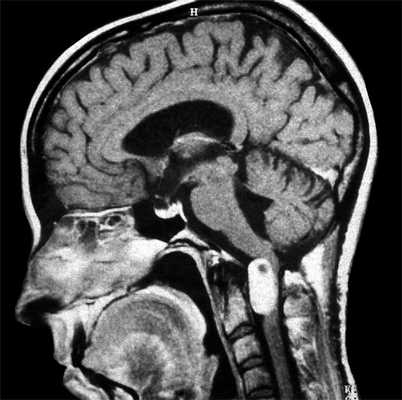

Кисты головного мозга и их диагностика

МРТ головного мозга. Т2-взвешенная аксиальная томограмма. Арахноидальная киста. Цветовая обработка изображения.

Кисты головного мозга в большинстве своем относятся к аномалиям развития. Некоторые образования, возникшие на почве нарушения развития, имеют сходные с кистами черты.

Арахноидальные кисты представляют собой скопление ликвора между листками расщепленной паутинной оболочки. Арахноидальная киста обычно не сопровождается другими мальформациями. Незначительная часть арахноидальных кист имеет приобретенное происхождение - следствие лептоменингита, операции или кровоизлияния. Частота составляет около 1% от внутричерепных образований. Соотношение полов М:Ж, как 4:1. Типичная локализация - средняя черепная ямка (в области Сильвиевой борозды 50%), межполушарная щель, мосто-мозжечковый угол (11%), за скатом или на уровне четверохолмия (10%), в области червя мозжечка (9%), реже в области межножковой и предмостовой цистерн (3%), а также супраселлярной и хиазмальной цистерн. Ретроцеребеллярная арахноидальная киста довольно часто встречаются за мозжечком и отличима от mega cisterna только по неизменённой задней черепной ямке. Содержимое кисты чисто ликворное, стенки гладкие, чётко очерченные, внутри кисты могут быть перегородки. Мелкие арахноидальные кисты очень трудно увидеть. Меняя ширину окна и его уровень на Т1-взвешенных МРТ изображениях можно заметить, что киста чуть светлее ликвора. Дифференциальная диагностика с эпидермальными кистами лучше осуществляется с помощью МРТ последовательности FLAIR. Эпидермальные кисты становятся яркими, в отличие от гипоинтенсивных арахноидальных.